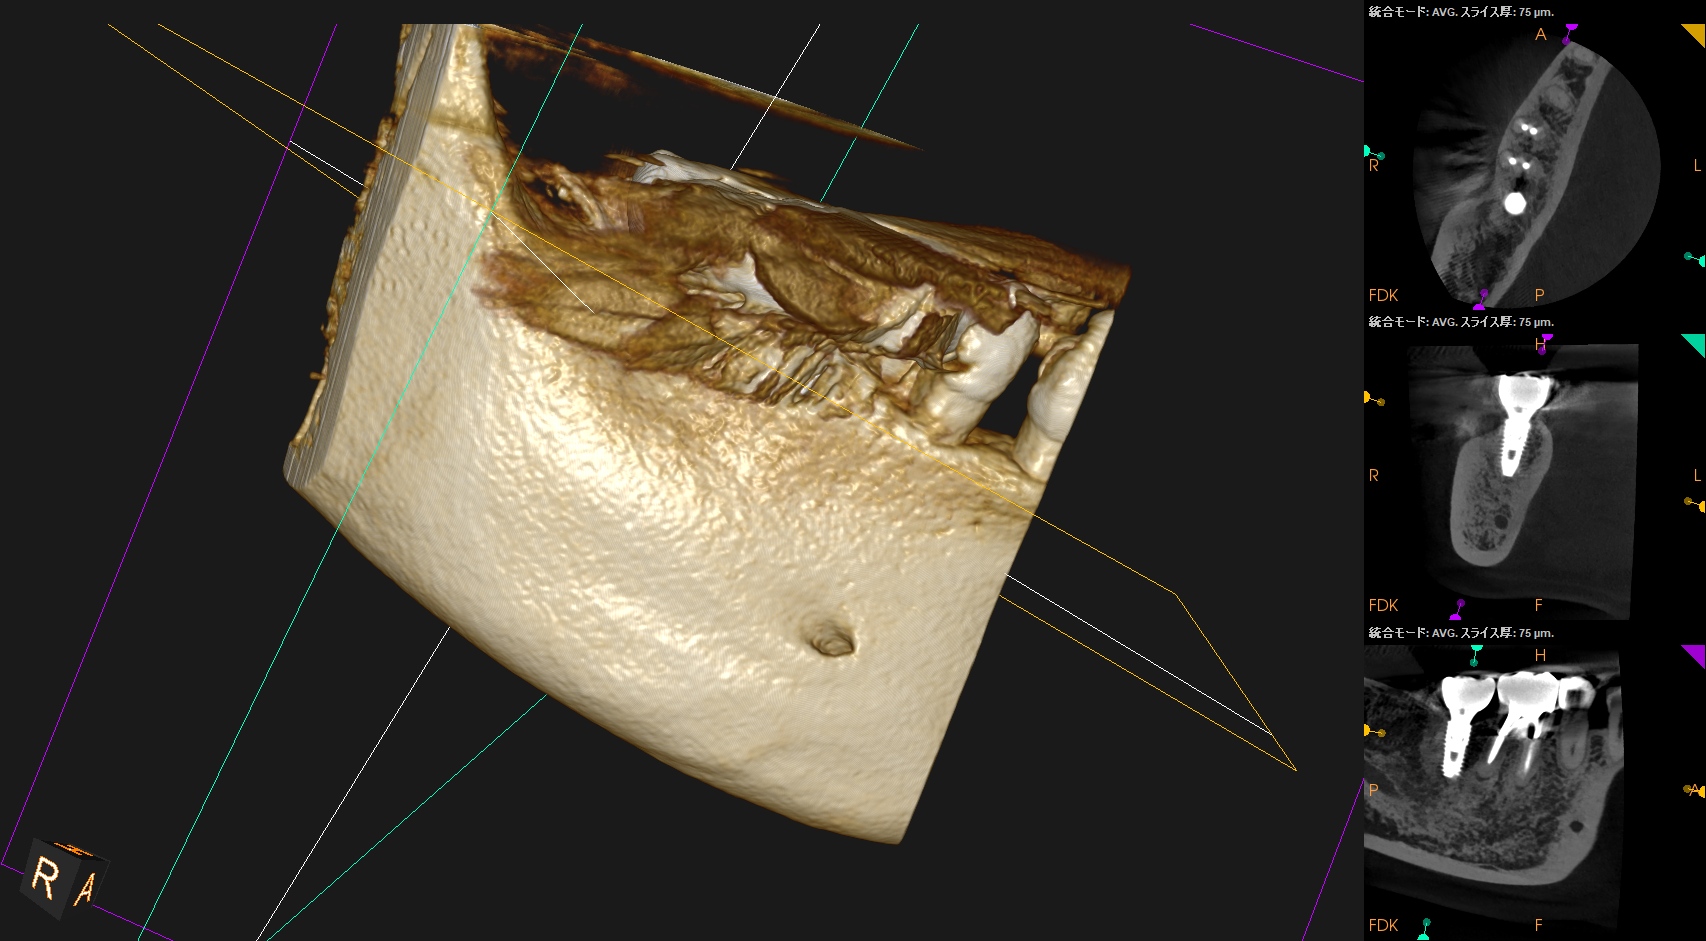

CBCT(2025.10.27)

MB

ML

DB

DL

MのApexに到達するにはCEJよりも12.5mm下方の歯槽骨を2mm削合(Osteotomy)しなければならない。

Apexを見つけたら3mm切断するがこの時の頬舌的な幅径が6.3mmだ。

リンデマンバーの半分よりも長い。

またDはApexに到達するには、CEJよりも13mm下方の歯槽骨を3mm削合する必要がある。